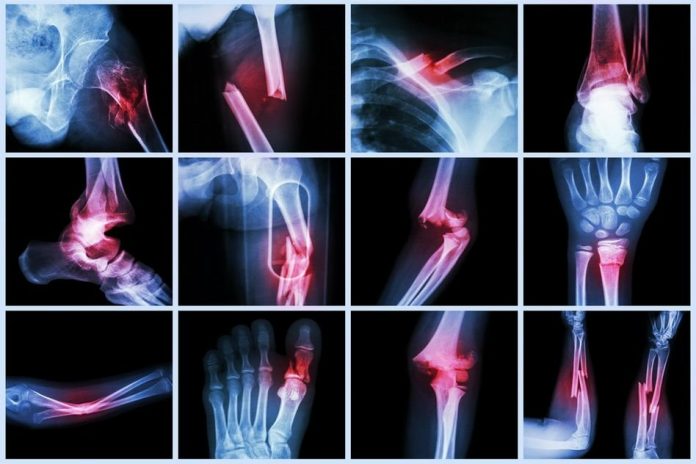

Fractura reprezintă o întrerupere completă sau incompletă a continuității osoase, cu sau fără deplasarea fragmentelor osoase.

• Examenul radiografic este mijlocul cel mai sigur pentru a pune în evidență o fractură, cu condiția unei bune execuții tehnice. El trebuie făcut sistematic, înaintea oricărei tentative de reducere, și, pentru a fi complet în aprecierea importanței deplasărilor, el trebuie efectuat cel puțin din două incidențe.